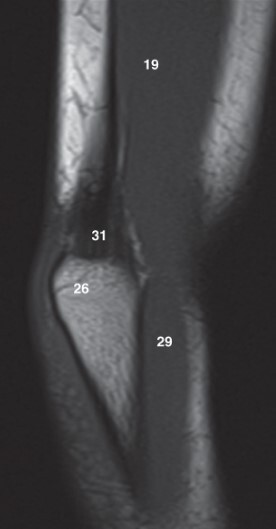

Label 19 and 26

A

19-Lt. Triceps brachii muscle

26-Olecranon process of lt. ulna